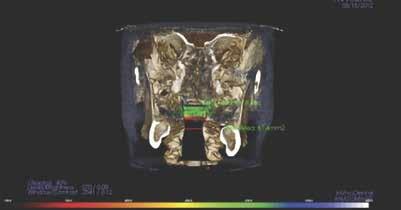

értékelik; azonban ritkán vizsgálják a betegeket az elzáródások eredetére vonatkozóan. Ennek eredményeképpen nagyon gyakran orrelzáródásuk van, és a légutak fizikális vizsgálata vagy képalkotó vizsgálata nélkül kapnak CPAP készüléket, amely a maszk szivárgásával kapcsolatos problémákhoz vezet. Az OSA hatékony kezelési tervének első lépése egy teljes fejre kiterjedő CBCT-vizsgálat elvégzése az elzáródás 4 pontjának meghatározására. (A 4 elzáródási pont (8. ábra) és a CBCT (i-CAT) segítségével történő értékelés részletes magyarázatát lásd az Orthodontic Practice US 2015. márciusi/áprilisi számában [16]). A páciens 4 obstrukciós pontjának – orr-szájpad, orr-garat, velopharynx és oropharynx – vizsgálata kimutatta, hogy a pozíciófüggő apnoe (nyelvalap és velopharynx) mellett orrdugulása is volt (lásd a 9. ábrán látható CBCT-felvételt). Az orrlégúti ellenállás és a BMI a legkorlátozóbb tényezők az OSA-behirdetés

tegek orális készülékterápiával (OAT) történő sikeres kezelésében [17]. Az orrlégúti elzáródás közvetlenül öszszefügg a nappali fáradtsággal [18]. Az i-CAT képalkotó szoftver lehetővé teszi az oropharyngeális légutak volumetrikus értékelését. Ennek a betegnek a kapott adatok alapján súlyosan veszélyeztetett légútja volt, minimum 61,3 mm-rel. A színskála azt mutatja, hogy az értékelés alsó határa 100 mm (9–11. ábra). Kezelési tervünkben OAT (EMA II), fül-orr-gégészeti konzultáció és egy nyomon követő alvásvizsgálat szerepelt. Az FDA által jóváhagyott alvásfogászati készülék 2012. szeptember 5-én került szállításra (12. ábra). A Sibilant Phoneme (Sziszegő fonéma) harapásregisztrációs technikát használtuk a készülék elkészítésének a kiinduló helyzeteként, mivel ez fiziológiai, nem pedig konstrukciós technika. Ez az egyetlen olyan harapásregisztrációs technika, amely bizonyítottan és szakmailag lektorált folyóiratban publikálva jelent meg. Ennek a harapásregisztrációs technikának lényege, hogy megnyitja a légutakat, de amely a legfontosabb, csökkenti azok összeesését [19]. Az OSA-ban szenvedő betegeknél a légzés kizárólag csak alvás közben áll le, ezzel szemben ébrenlét közben soha nem áll le. Így az oropharyngealis légutak térfogata kevésbé fontos, mint azok összeesése. Ez azt jelenti, hogy ritkán van szükség titrálásra, ha a fonetikus harapásregisztrációt kiindulási pontként használjuk. Ez a páciens tökéletes példa erre, mivel az ő készülékét soha nem kellett titrálni. Az orofaringeális térfogatok (13. ábra) az ébrenléti kiindulási állapotban és a harapásregisztrációval csak kis különbséget mutatnak, azonban az

mény volt, hogy az oropharyngealis légutak nagyobbak voltak az orrműtét után. A minimum 61,3 mm-ről 213 mm-re nőtt (15. ábra)

9. ábra: A 3D-s vizsgálat orrkagyló- és orrsövényproblémákat mutat.

10–11. ábra: Légutak számításai különböző nézetekben.

13. ábra: A légutak méretei (balra) és a harapásregisztráció (jobbra).

14. ábra: Jelentős légáramlás-növekedés. – 15. ábra: Légutak méretének növekedése a kezelés után.